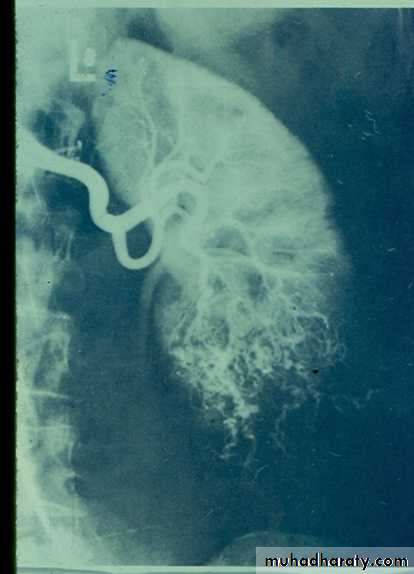

• IVU: Early stage –cobble stone Later filling defects due to graneulomatos papilloma Carcinoma is important complication Ureters : dilated and tortuousIn early stage hydroureter and hydronephrosis + refluxSPACE OCCUPING LESION